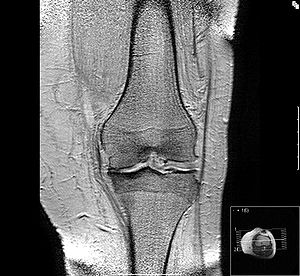

Die Magnetresonanztomografie kann bei Kniearthrose folgende Zeichen sichtbar machen:

- Verdickung der Gelenkschleimhaut (Synovialitis),

- Wassereinlagerungen im Knochen (Knochenödeme),

- Unterscheidung zwischen begrenzt (fokal) oder tiefgehendem Knorpelschaden und

- Schleimbeutelentzündung am Kniegelenk (Bursitis).

Die Veränderungen des Kniegelenks bei einer Kniearthrose betreffen nicht nur den Gelenkknorpel. Auch alle anderen Strukturen des Kniegelenks sind von der Arthrose betroffen. Die Untersuchung dieser arthrosetypischen Veränderungen an Knochen, Meniskus, Kreuzbändern und Seitenbändern des Kniegelenks ist für die Diagnose und Therapie der Kniearthrose wesentlich.